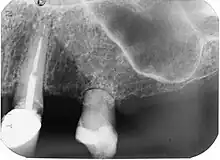

| Diagnostic method | Dental examination, X-rays |

It may also present as an incidental, radiographic finding. Radiographically, a radiolucent area of uniform density within the root canal may be visible with well-defined borders. Canal walls may appear sclerosed, thus the outline of pulp chambers or root canals may not be followed through the lesion. Lesions may also be oval radiolucencies that are continuous with the canal walls.

External resorption is the loss of tooth structure from the external surface of the tooth and is further subcategorized based on its etiology.[16]